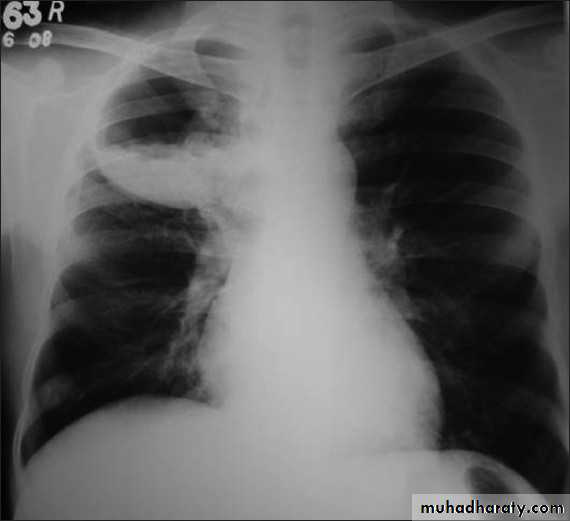

Tension pneumothorax

56.tension pneumothorax left sided aspect

57. tension pneumothorax right sided aspect